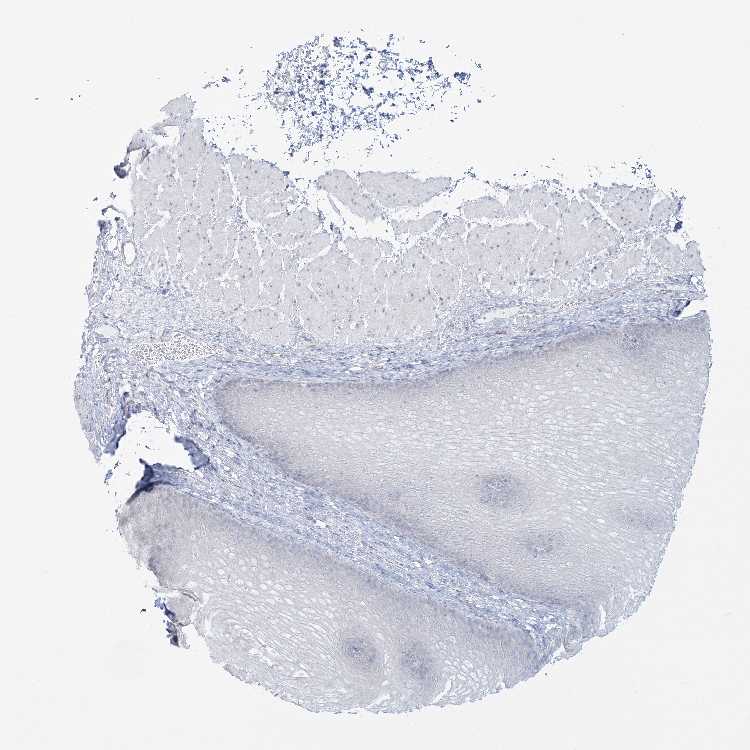

ESOPHAGUS - Antibody stainingi

Antibody staining in the annotated cell types in the current human tissue is reported as not detected, low, medium, or high, based on conventional immunohistochemistry profiling in selected tissues. This score is based on the combination of the staining intensity and fraction of stained cells.

Each image is clickable and will lead to virtual microscopy that enables deeper exploration of all samples and also displays staining intensity scores, fraction scores and subcellular localization as well as patient and tissue information for each sample.

Antibody HPA036340

Squamous epithelial cells Not detected